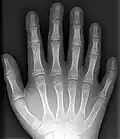

-

Röntgenfoto van hand met 6 vingers -